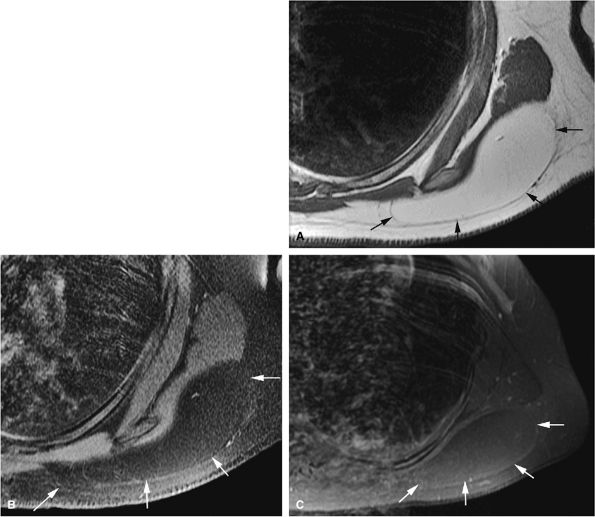

FIGURE 14-24 ● Periosteal (i.e., juxtacortical) chondroma located in the proximal humerus is seen on coronal proton density-weighted (A), fat-suppressed T2-weighted fast spin-echo (B), and contrast-enhanced (C) images. Central osseous tissue is low in signal intensity on the proton density and fat-suppressed T2-weighted sequences (arrows).